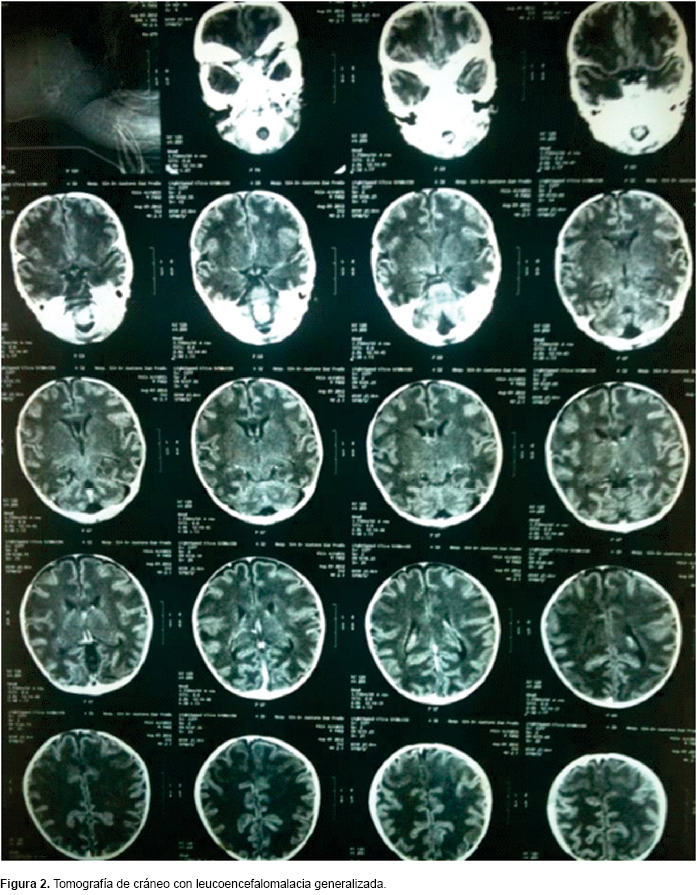

El paciente persistió con crisis convulsivas tónico-clónicas (Figura 1), por lo que se inició protocolo de estudio. Se realizó tamiz metabólico ampliado en el que no se identificaron alteraciones o errores innatos del metabolismo. Cultivos citológico, citoquímico y de líquido cefalorraquídeo, normales. Tomografía de cráneo con leucoencefalomalacia global, probablemente secundaria a encefalopatía hipóxico-isquémica (Figura 2). Al realizar EEG, se identificó patrón de brote-supresión (BS), por lo que se estableció el diagnostico de SO por servicio de neurología pediátrica (Figura 3). Se inició tratamiento con vigabatrina a 80 mg/kg/día y con ácido valproico a 20 mg/kg/día, logrando el control de las crisis convulsivas. Se refirió a un hospital de segundo nivel para continuar su manejo.